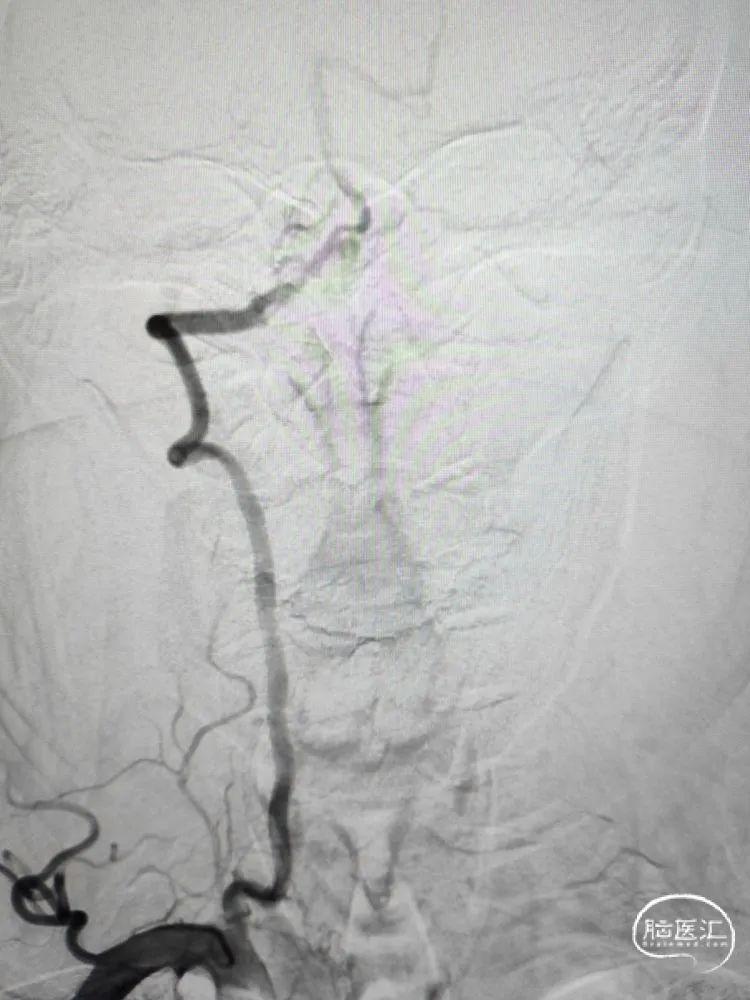

术前影像学检查:全脑血管造影检查提示右侧椎动脉V5段(颅内段)夹层动脉瘤。

动脉瘤大小约5.45mm×7.31mm,动脉瘤远端椎动脉汇合前管径约2.77mm,动脉瘤近端V4段管径约3.80mm,V5段全长约35mm,对侧椎动脉正常。

正位造影